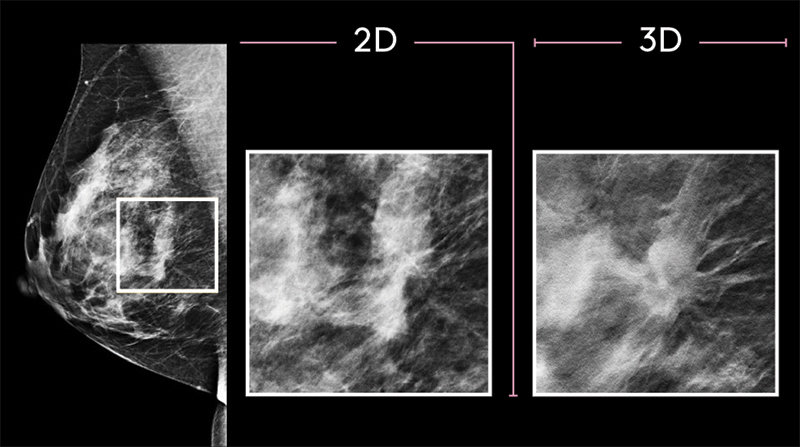

3-D mammography screening

At MetroHealth, 3D mammography (3D breast tomosynthesis) is our standard screening mammogram protocol for every patient. 3D mammograms provide a more accurate exam by looking at the breast tissue in sections, significantly improving early breast cancer detection and lowering the need for follow-up imaging. In fact, multiple clinical studies show that 3D mammography finds 40% more invasive cancer not seen with conventional 2D mammography. We use the lowest dose of radiation available for 3D mammography in this advanced screening tool.